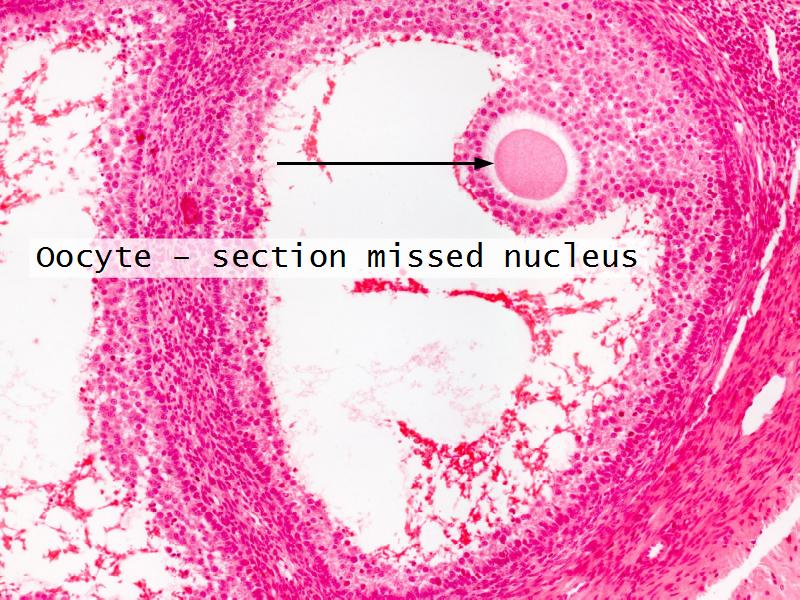

- Ovary

- Slide 89/106: Ovary